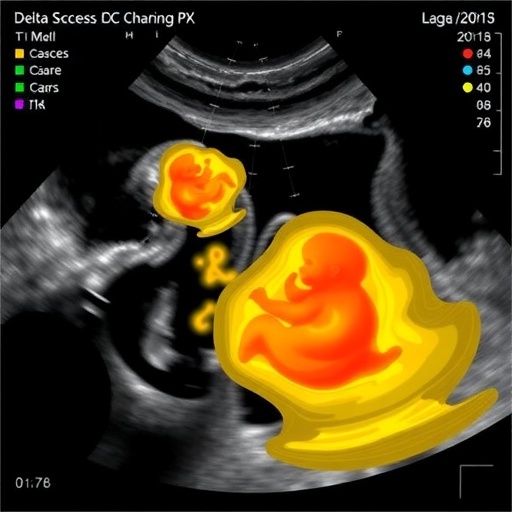

The study, published in the Journal of Ovarian Research, explores the intricate relationship between ultrasound imaging and embryo viability. Traditional methodologies often lack the ability to process and interpret the vast amounts of data generated during embryonic assessments, leading to less informed predictions. This is where the new delta ultrasound radiomics model steps in, offering a novel method to analyze ultrasound features quantitatively. By leveraging advanced algorithms, this model discerns critical patterns that may predict embryo development and success rates with greater accuracy than ever before.

At the core of the model lies the concept of radiomics, which translates medical images into high-dimensional data. This data can then be analyzed using machine learning techniques to uncover hidden correlations between ultrasound characteristics and clinical outcomes. The research team employed a variety of machine learning algorithms to evaluate the performance of their model, thereby identifying which features held the most predictive power in determining the likelihood of live births following embryo transfer.

Understanding the technical framework of this model is crucial for appreciating its implications. The delta ultrasound radiomics model analyzes changes or ‘deltas’ in the ultrasound images of embryos, offering insights into how these changes relate to live birth success. For instance, the model assesses various parameters of embryo morphology, such as blastocyst expansion and inner cell mass quality, which are instrumental in determining the viability of embryos post-transfer. This nuanced understanding assists physicians in making more informed decisions regarding embryo selection and transfer.